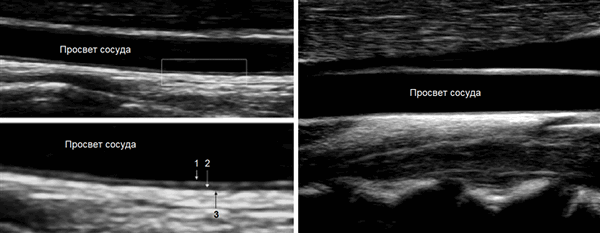

В просвете вен в/к можно видеть клапаны, место первого клапана непостоянное, чаще в плечевой вене.

Створки клапанов должны быть тонкими и двигаться в зависимости от направления движения крови.

Стенку сосуда исследуют линейным датчиком 7-18 МГц. Когда УЗ-луч направлен под 90°, максимальное отражение и контрастность изображения.

КИМ составляют интима и медиа сосудистой стенки. Адвентиция сливается с окружающими тканями. Измеряют КИМ ОСА и ВСА на 1 см ниже и выше бифуркации.

Интима представлена эндотелием и субэндотелием; медиа — в ОСА преимущественно эластичная строма, в ВСА с выраженным мышечным компонентом.

КИМ лучше видно на удаленной стенке — анэхогенная медиа между гиперэхогенной интимой и адвентицией. В норме 0,5-0,8 мм, у пожилых 1,0-1,1 мм.

В М-режиме диаметр сосуда измеряют между интимой и адвентицией в систолу и диастолу.